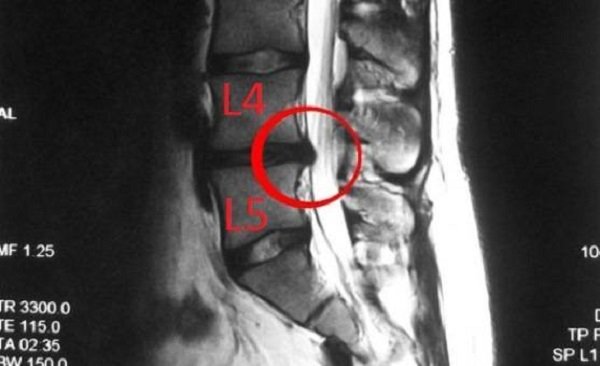

Выбухание фиброзного кольца является второй стадией остеохондроза и чаще образуется в поясничном либо пояснично-крестцовом отделах, поражая позвонки S1 и L4, L5. Несколько реже патология диагностируется в шейном сегменте и лишь иногда встречается в грудном.

В настоящее время при диагностировании межпозвонковой протрузии наиболее значимым исследованием признана магнитно-резонансная томография. Процедура идеально подходит для выявления аномалий диска и оценки состояния других мягких тканей спины. Но при необходимости исследовать структуру позвонков МР-томография отстает от КТ.